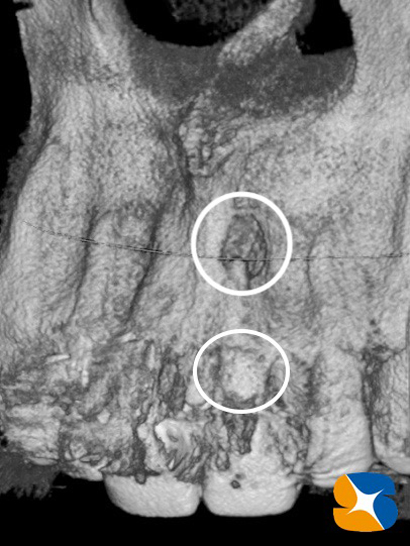

早速、歯科用CTで患部をチェック。問題のある歯の根の先は、ビー玉状に骨が欠落していることが確認できました。

CTを再チェック。やはり、歯の根のヒビに沿って、骨も溶けて無くなっている(下の丸い白円)ことが分かりました。

患者様には、「歯の根の上と下の両サイド(白い2つの丸線)から骨が無くなっている。そのため歯を支える骨が真ん中のみのため、歯が動いていたと思われます。」と説明しました。